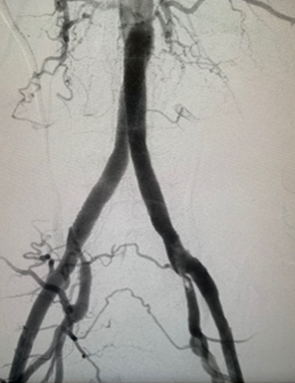

Resultado final

En situaciones moderadas o severas, procedimientos mínimos invasivos se pueden llevar a cabo como angioplastia, la dilatación de estas zonas con un balón intravascular, con la colocación de stent. Los stents son un tipo de resorte que, generalmente, comprime la placa hacia la pared y crea una luz más amplia del vaso sanguíneo.